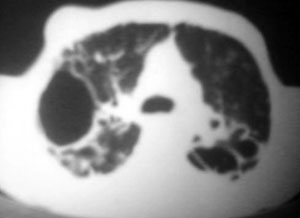

以下是引用逸风在2006-9-12 14:57:00的发言:[br]ct显示双肺上叶点片状及纤维索条状密度不均影,肺野外带近胸膜可见大小不等的含气空腔,壁略厚,境界清晰,未见液平面,中下肺野散在小片状及点状高密度影;纵隔内显示点状钙化,未见明显淋巴结肿大,构成胸廓诸骨未见明显异常.[br]诊断意见:1.双肺结核合并支气管播散;2.双肺上肺大泡.